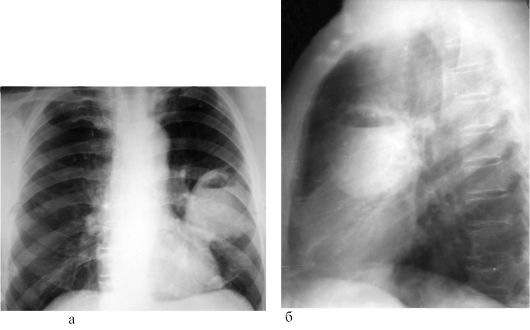

Рентгенологические изображения и синдромы патологии легких

Раздел: Кадры-подсказки